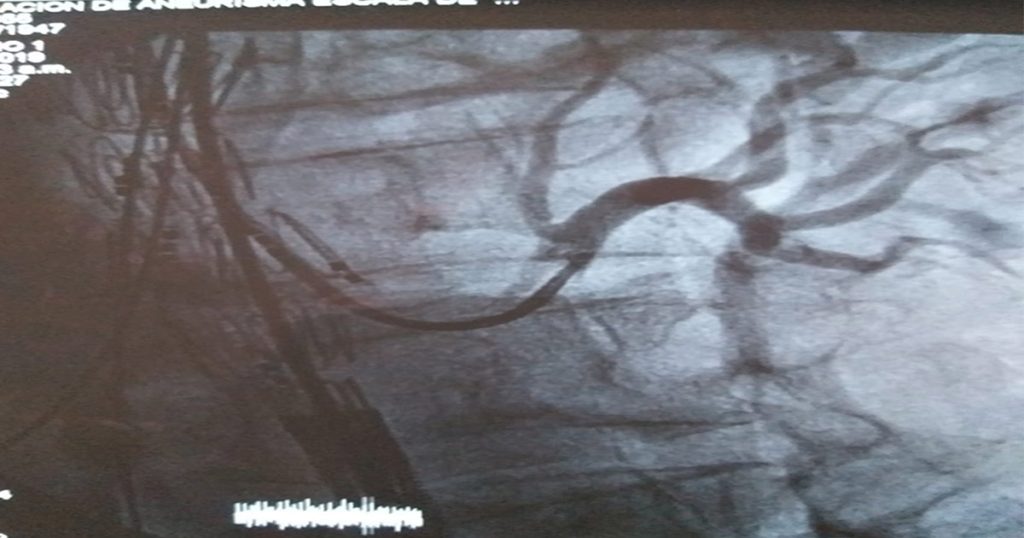

Así que el usuario es llevado al área de Hemodinamia para realizar el procedimiento quirúrgico y las áreas de anestesiología, cardiología y vascular proceden a realizar la operación. En primera medida, se realiza exploración de arteria axilar y angioplastia o arterioctomía de vasos abdominales.

Posteriormente, se hace exploración arteria bilateral inguinal y junto a la arteria axilar se pasan dos introductores para que guías hidrofílicas más dos landerquist dan paso a la prótesis ‘T Branch de Cook’ el cual es liberado en la aneurisma y así reducir la inflamación arterial. Al finalizar, se hace canulación de arterias como la abdominal y renal, entre otras ramificaciones del sistema circulatorio.